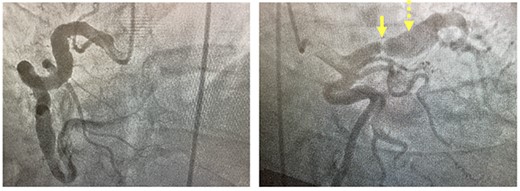

His initial troponin was not elevated although the electrocardiogram showed new ST depressions in the medial precordial leads and subsequent troponins were elevated. He was transferred to our institution and underwent left heart catheterization which demonstrated a right dominant circulation with ectasia of the right coronary artery, a fusiform aneurysm of the left anterior descending coronary artery (LAD) and a generous-sized left circumflex coronary artery (Fig. 1). There was a 99% stenosis of the LAD with post-stenotic dilatation up to 13 mm with gradual normalization over the course of the remainder of the vessel. An echocardiogram showed a left ventricular ejection fraction of 35% without valvular pathology. Percutaneous coronary intervention (PCI) was thought to be a poor option because the distal portion of the stent would not oppose the wall of the vessel but be ‘floating’ in the aneurysmal portion of the artery pre-disposing thrombus formation. Therefore, in anticipation of operative intervention, a computed tomography scan was done to further define the anatomy. The scan demonstrated extensive wall thickening and contour irregularity suggestive of diffuse coronary arteritis (Fig. 2). The study also showed a dilated main pulmonary artery up to 46 mm and an aberrant right subclavian artery coming off the distal aortic arch and passing behind the esophagus.

Coronary angiogram. Left panel: injection of fusiform aneurysm of right coronary artery. Right panel: coronary angiogram injection of the left-sided coronary circulation with solid yellow arrow pointing to tight left anterior descending stenosis and dotted yellow arrow pointing to post-stenotic aneurysm.